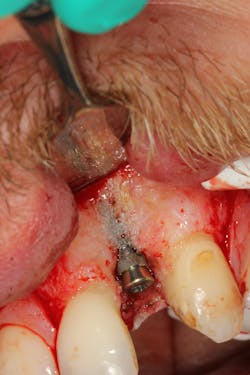

This surgical video demonstrates removal of a tooth with loss of buccal plate and grafting of the remaining socket with Geistlich Bio-Oss Collagen and Geistlich Bio-Gide to preserve the ridge for implant placement.